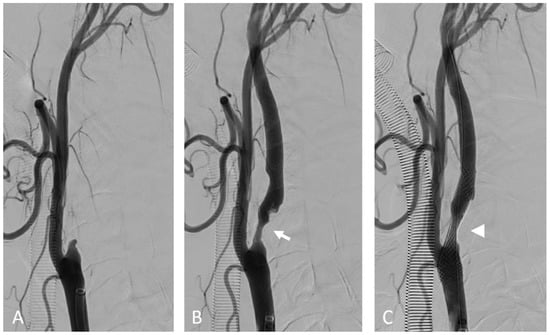

Figure 4.

Internal carotid artery occlusion, digital subtraction angiography: acute thrombotic occlusion of the left internal carotid artery (A) causing sudden neurologic deficit in a 77-year-old patient. The serigraphy performed after mechanical thrombectomy and recanalization of the artery (B) highlights an ulcerated atherosclerotic plaque of the carotid bulb (arrow). After the administration of intravenous boluses of antiplatelet agents and heparin, a self-expanding stent (arrow) was placed in correspondence to the ulcerated plaque (C).